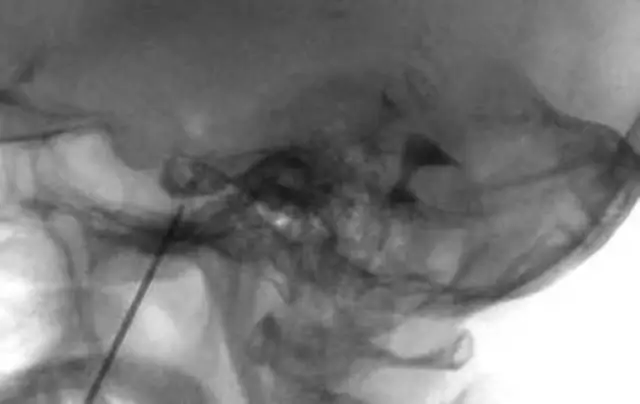

图1. 一旦X线透视确定了穿刺针的位置,且证明了有脑脊液流出,就要在患者半坐位下行甲泛葡胺脑池造影术。脑池造影图也可用来评估三叉神经池的容积,并且估计甘油的合适用量。

然后病人取半坐位,体位的改变有可能导致穿刺针移位,这时常需要再次摄片。然后需要在X线透视仪引导下以0.05mL为增量逐渐注射造影剂,直至造影剂从三叉神经池溢出。使用对比剂的量一般为0.25-0.40mL。